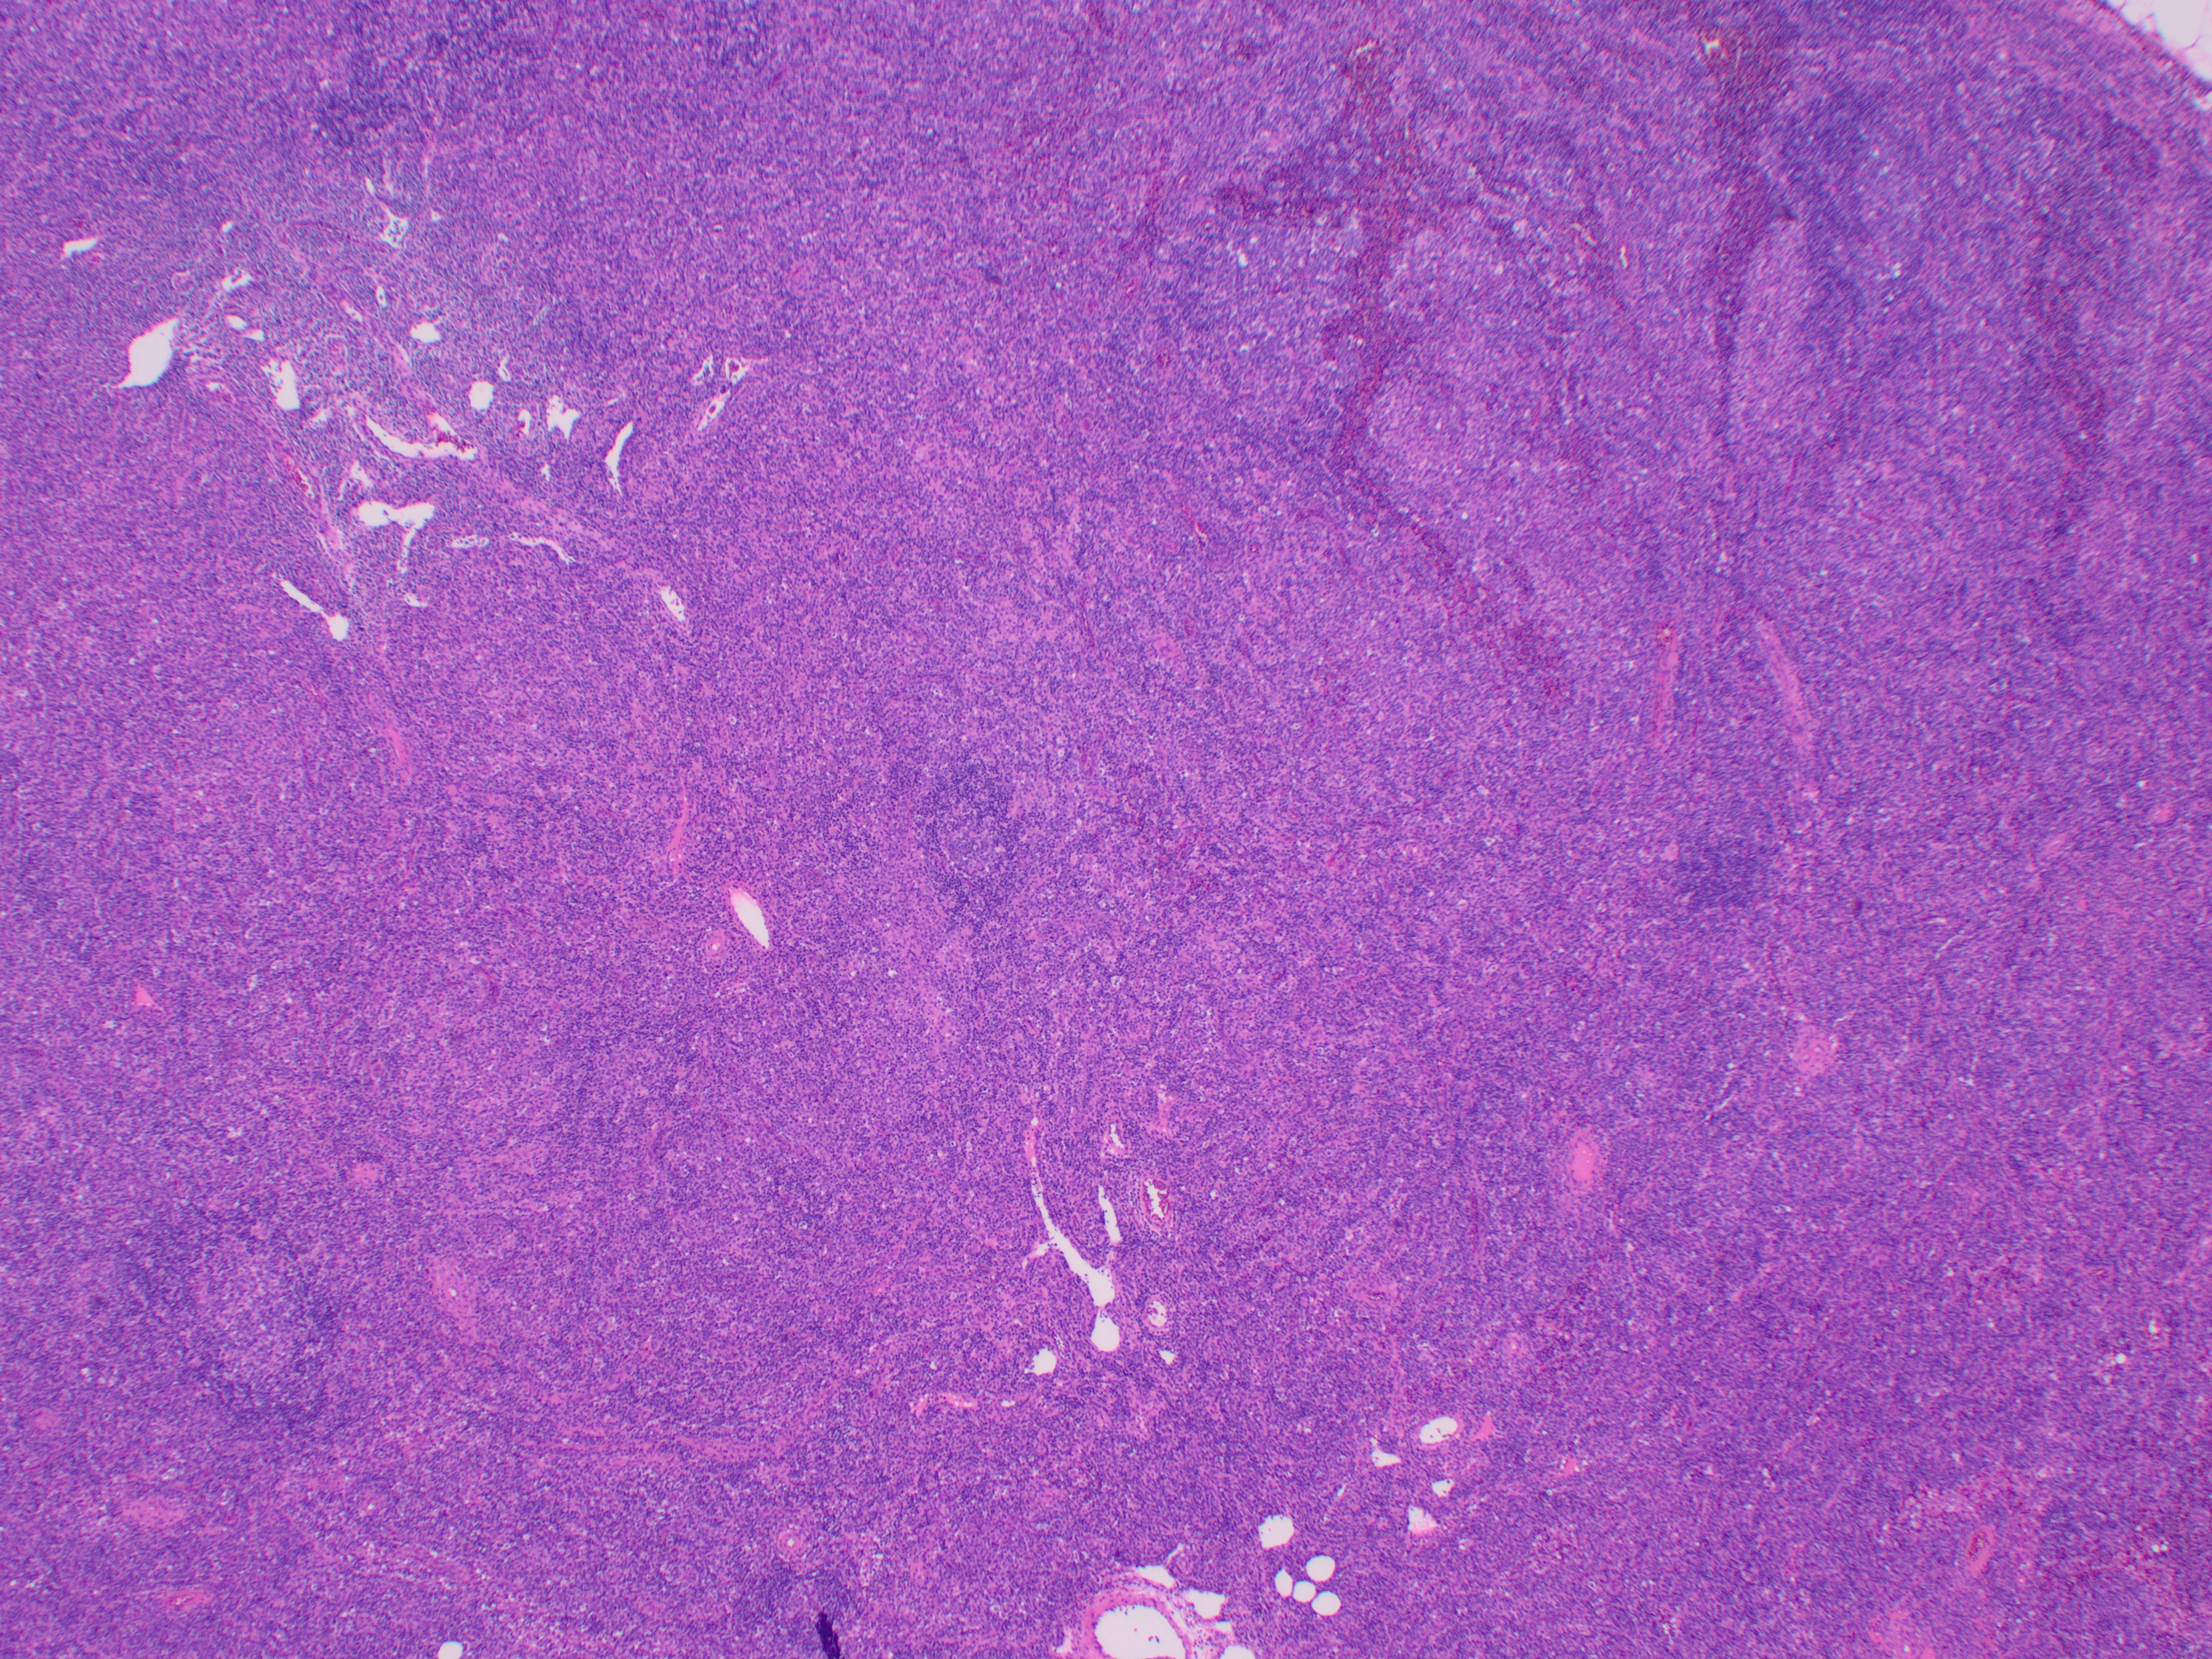

81-year-old female with a remote history of follicular lymphoma was undergoing evaluation for possible disease recurrence when an incidental right breast mass was identified.